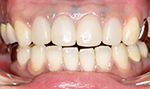

症例1

初診で前歯の保険の差し歯が変色し形も色も悪いのでセラミックで治したいと希望した患者さんです。

術後

患者さんは女性で柔らかい感じにしたいと希望がありましたので少し丸みをだして作りました。患者さんは満足しております。

術後4年経過

タバコを吸う方ですが歯の色の変色や着色また歯肉退縮もなく歯垢の付着もありませんでした。